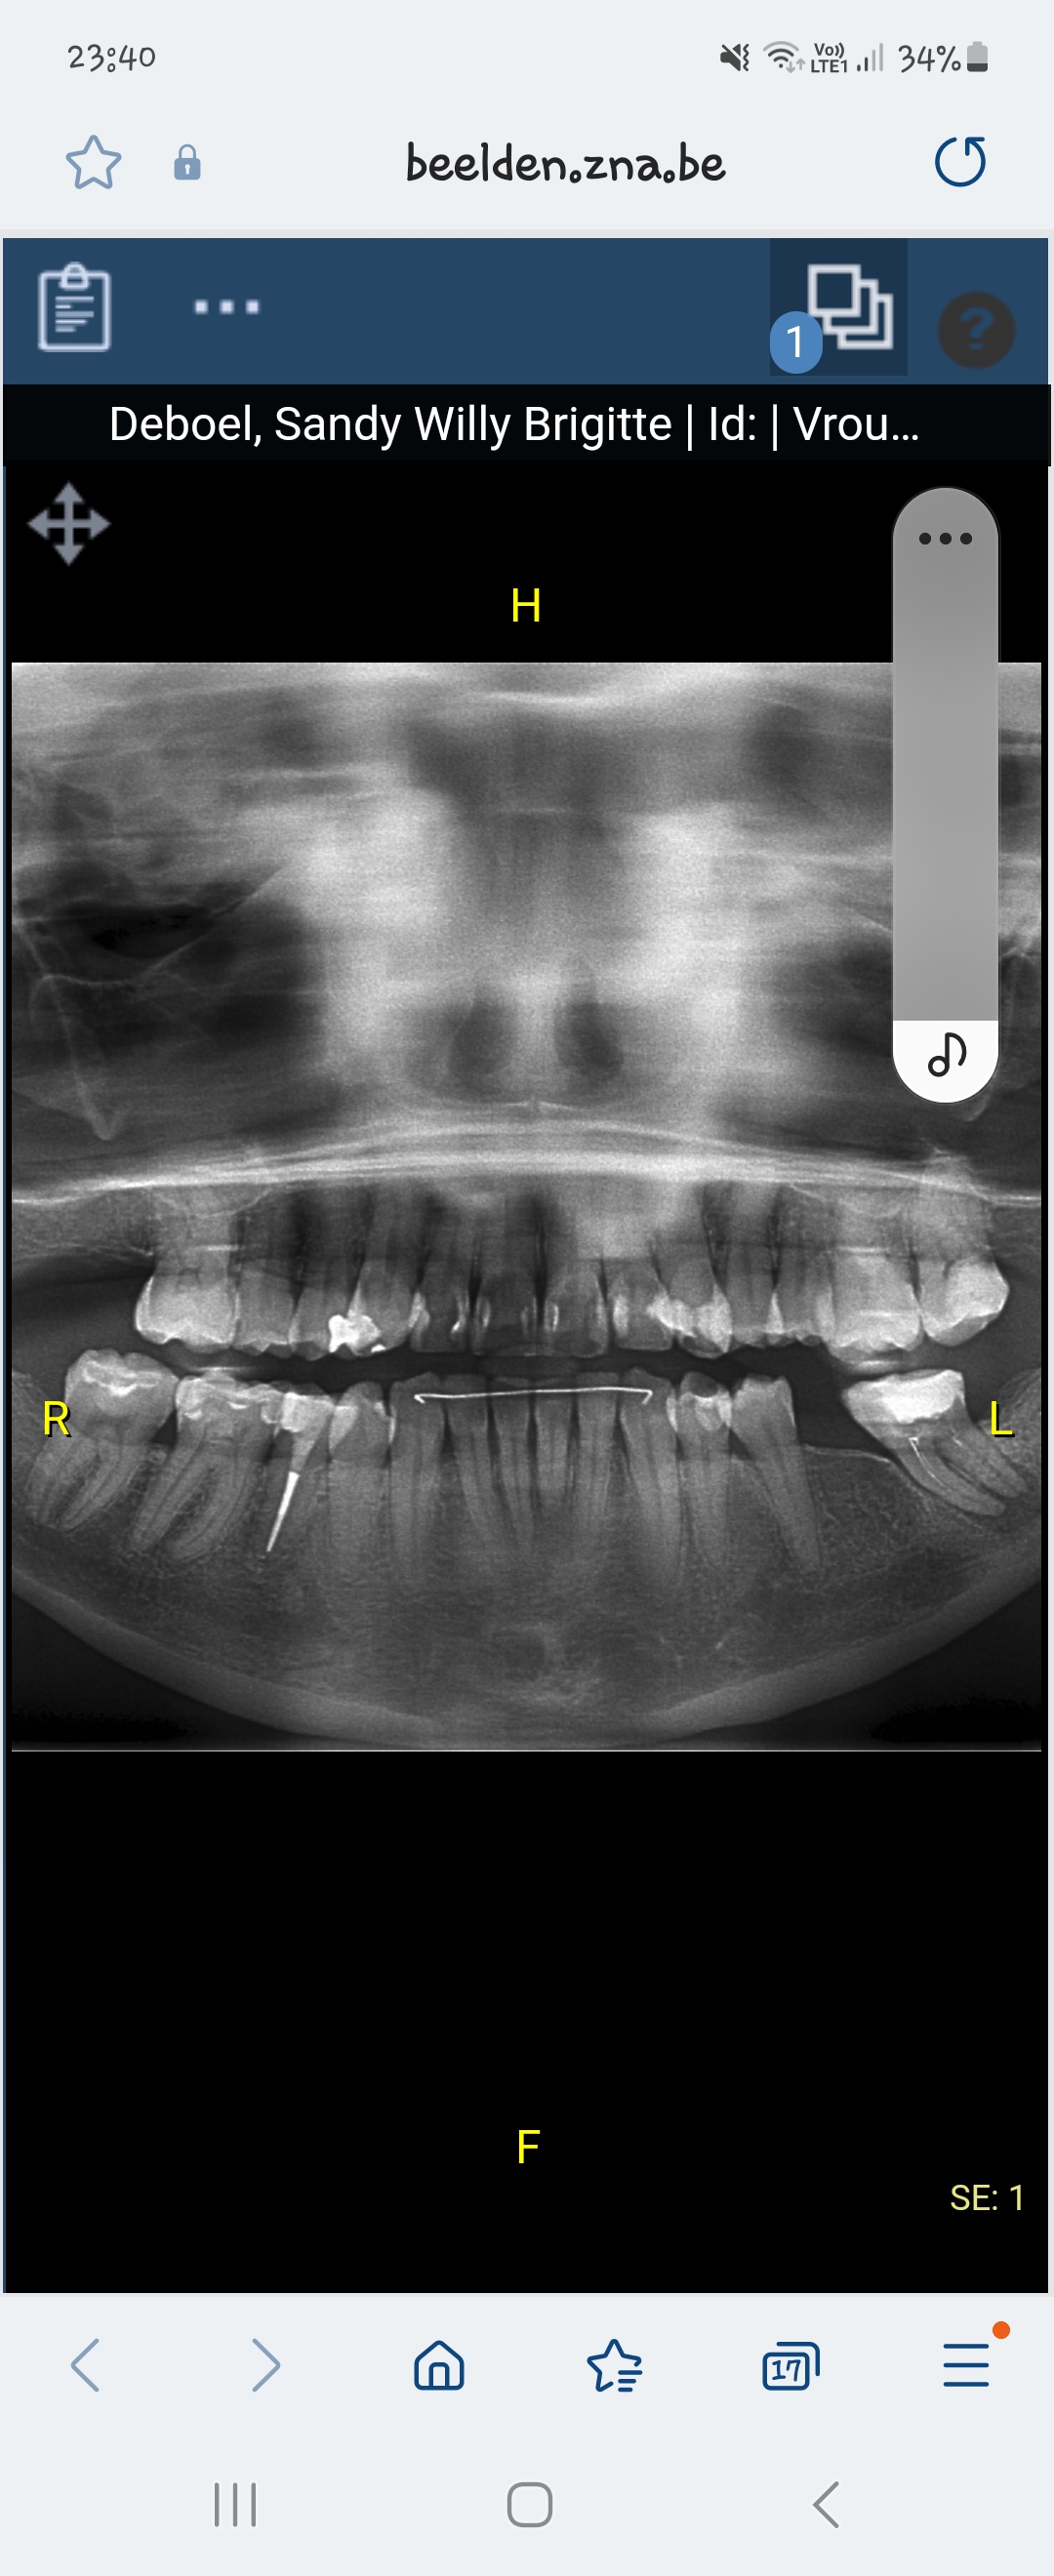

Hoi, het was links onder de laatste kies. Zoveel moeite was het niet aangezien deze al kon bewegen. Op vorige rx foto's was er wel een periapicale radiolucentie ofzoiets te zien, een zwarting. Ze zieden dat ze alles hebben proper geschraapt(dat was een naar gevoel) ik mocht normaal de 1ste 3dagen niet spoelen van de arts. Maar de dag erna heb ik dit wel zeer voorzichtig gedaan na het eten uit schrik voor ontsteking. Ook als ik men hoofd omhoog doe trekt dit in men onderkaak. Ik zal een foto van de rx erbij plaatsen. Mvg

Links onder de 37.... flinke zwarting aan de wortel punt. Als ik een zwarting zie dan wordt een wortelkanaal behandeling gedaan anders krijgt men er vroeg of laat toch last van...niet pas behandelen als men klachten heeft zeg ik ...voorkomen beter dan...is een cliche.. Nu duidelijk zwarting bij een niet voldoende gereinigd/gesloten kanalen in de 37...dat geeft problemen. Is geen herbehandeling overwogen ??? ik weet natuurlijk niet alle details.Nu dat de 37 verwijderd is...hoe gaat u de 46/47 vervangen...?. Anders groeien de 16/17 naar beneden door gebrek aan steun en u heeft geen kauw functie bij die kiezen.